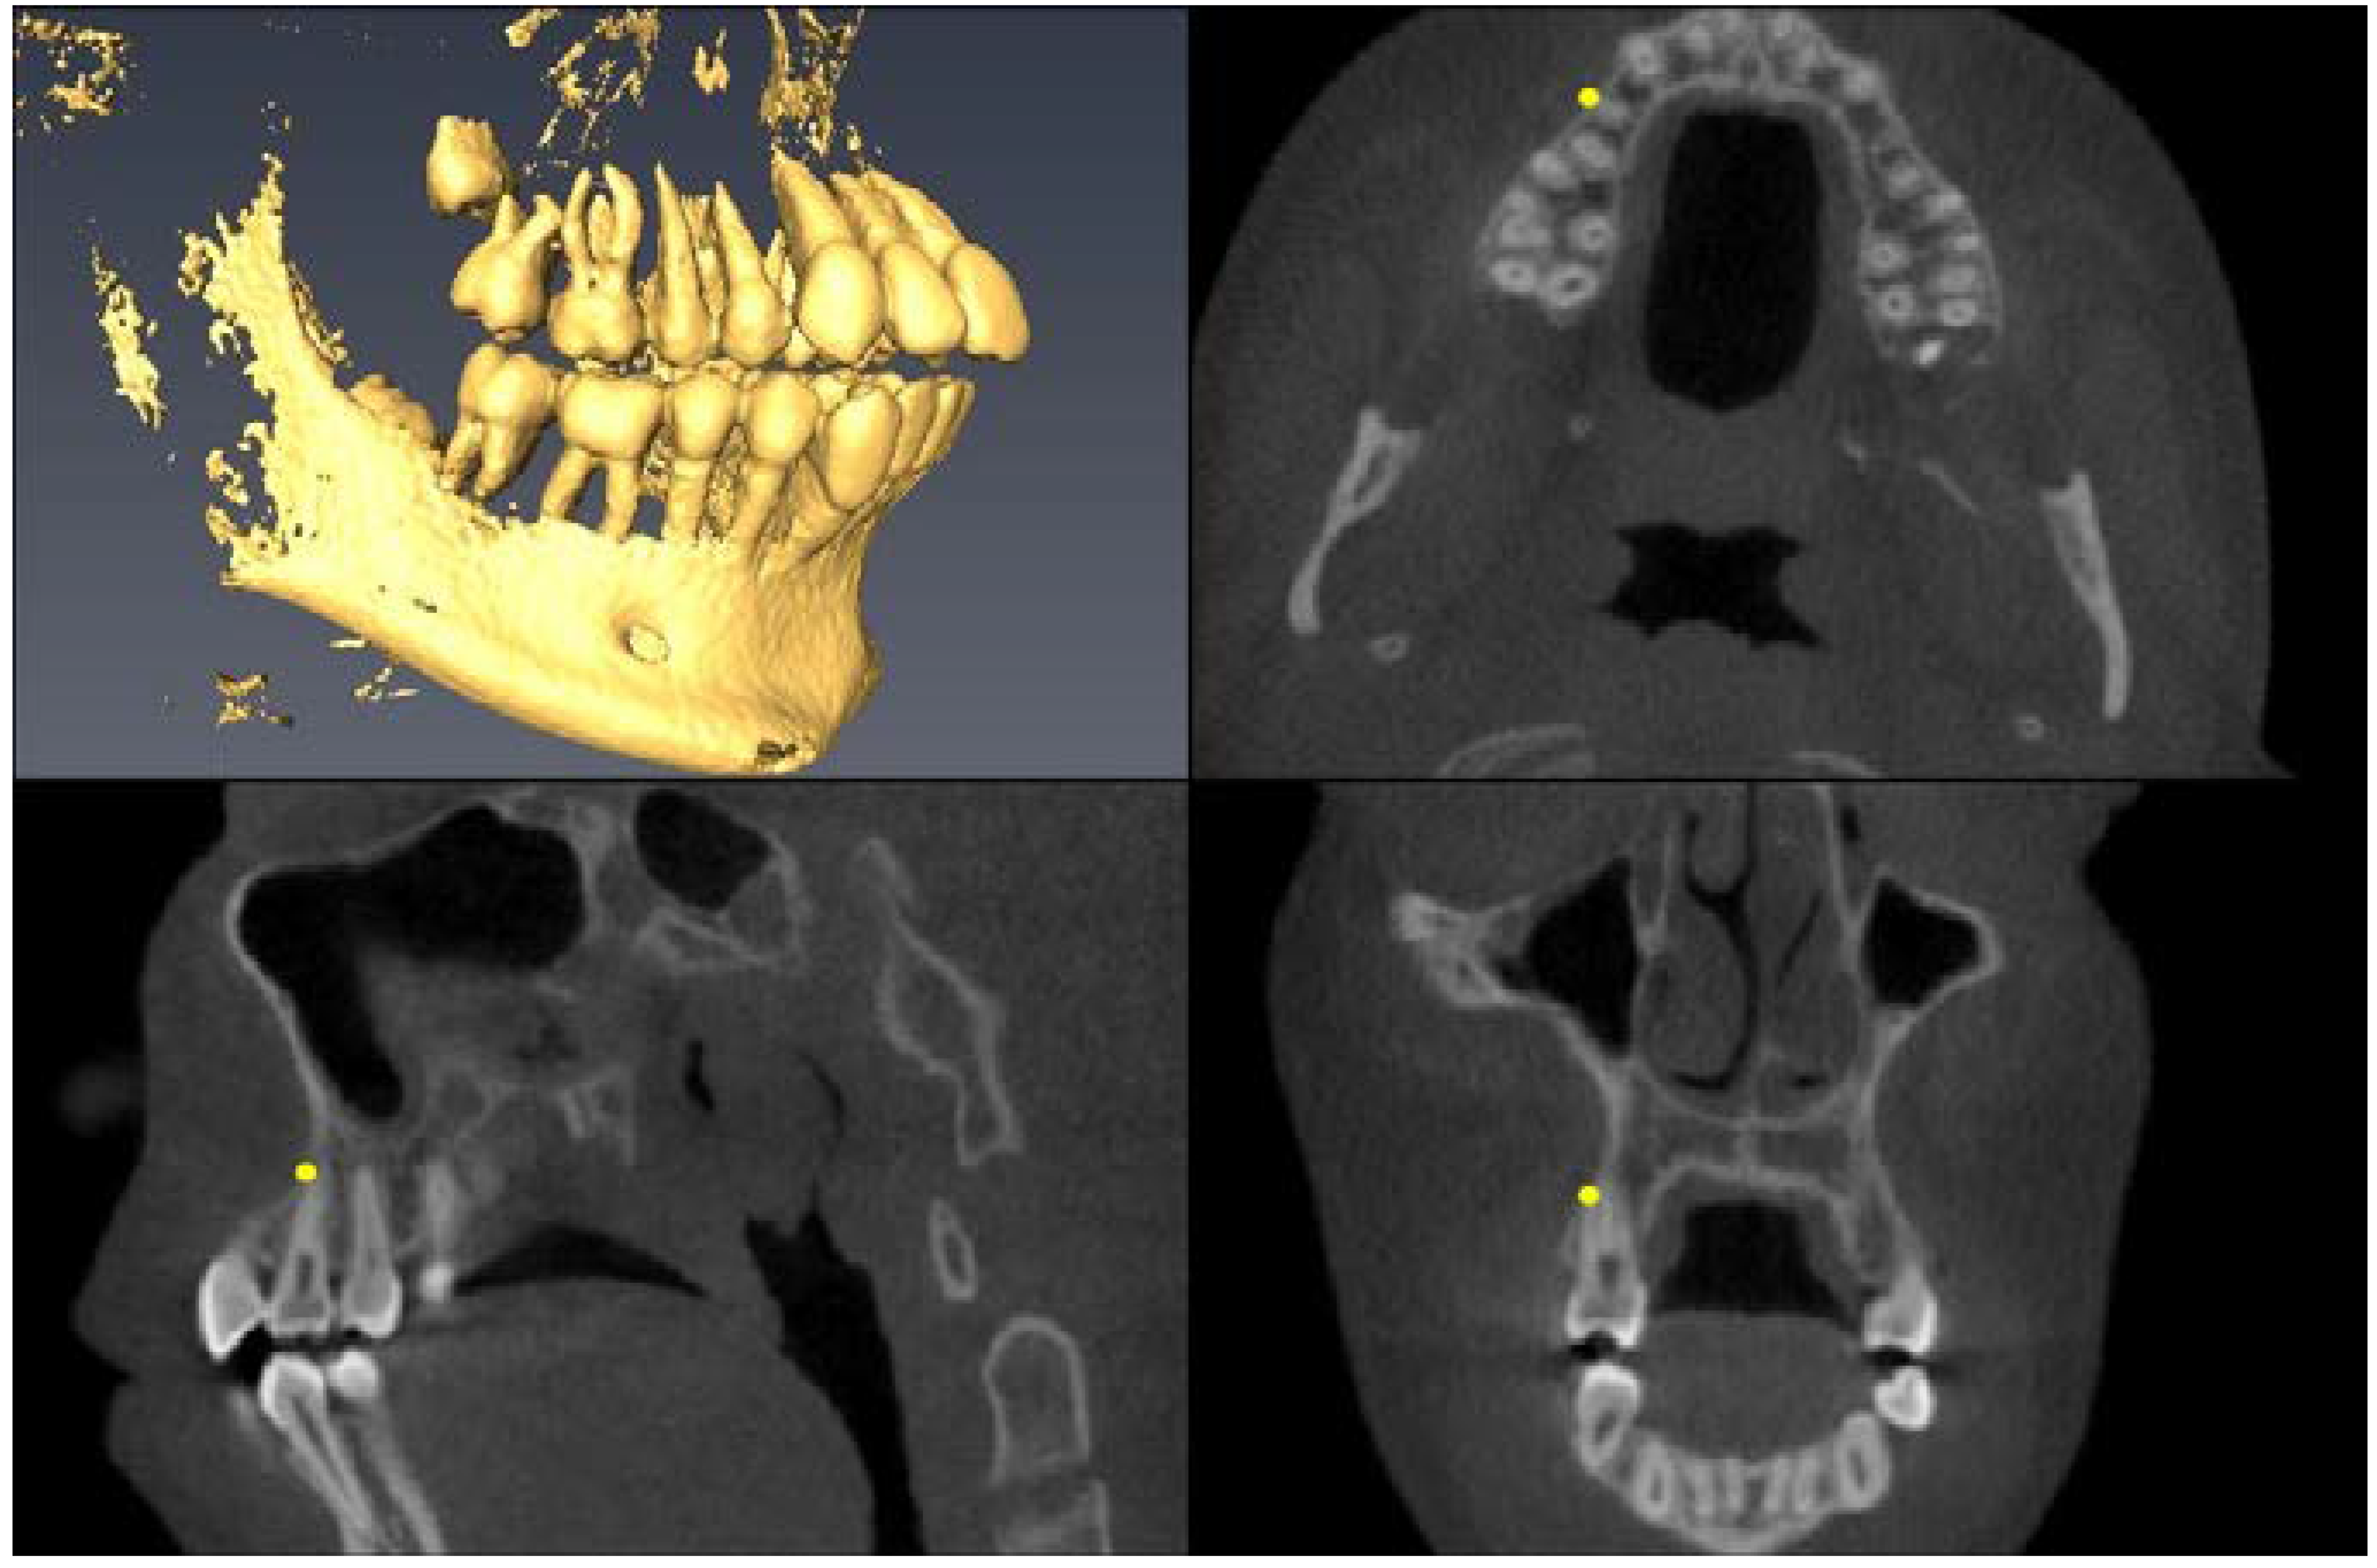

| Landmark Description | 3D View (Upper Left), Axial View (Upper Right), Sagittal View (Lower Left), Coronal View (Lower Right) |

| Upper First Molar Pulp Chamber =center of largest cross-sectional pulp chamber area | ![]() |